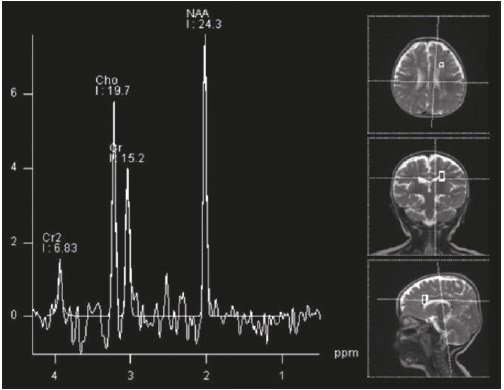

Las imágenes cerebrales, analizadas por un segundo neurorradiólogo, fueron informadas como sugestivas de noxa perinatal de posible origen hipóxico-isquémico; en los controles siguientes no se evidenció progresión de las lesiones, ni aparición de un patrón sugestivo de alguna de las leucodistrofias de origen metabólico (Figuras 1 y 2). La espectroscopia por RMC fue normal (Figura 3).

Las imágenes en la RMC cerebral dan información importante; las lesiones que alteran la sustancia blanca y que empeoran en controles sucesivos, unidas a regresión del neurodesarrollo, ayudan al diagnóstico clínico de leucodistrofia y hacen necesario hacer el diagnóstico diferencial con aquellas entidades asociadas a un defecto metabólico específico, y con las debidas a otras causas como las hipomielinizantes o las que presentan síntomas sistémicos característicos8)(9)(10. La paciente no presentó cuadro de regresión del neurodesarrollo, sino retraso psicomotor desde muy temprana edad que, pese al mal control de las crisis epilépticas, ha ido evolucionando hacia la adquisición lenta de hitos del desarrollo y no a la pérdida de los mismos como sucede en las enfermedades degenerativas de origen metabólico con afectación de la sustancia blanca. Existen leucodistrofias de presentación connatal, que son de curso progresivo, con manifestaciones visuales, auditivas y multisistémicas, pero esta no es una opción diagnóstica en la paciente. La ausencia de un patrón radiológico compatible con alguno de los EIM11)(12, así como el carácter estático de las lesiones que sugieren gliosis como resultado de un evento antiguo no progresivo, sumados a la espectroscopia normal por RMC, disminuyen la posibilidad de EIM en esta paciente.